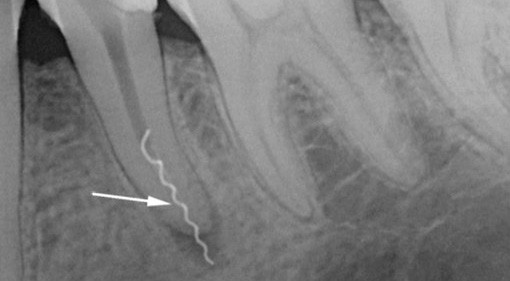

Um homem de 35 anos foi ao dentista com queixas de inchaço das gengivas na área do dente esquerdo por baixo, que periodicamente passa sozinho. Da história médica: o dente foi tratado anteriormente nos canais, a coroa de metal e cerâmica foi colocada há cerca de 2 anos. Os diagnósticos de inspeção visual, percussão, EDI e radiografias mostraram que o dente está localizado sob a coroa com o nervo removido e na região do ápice da raiz anterior 3,6 do granuloma do dente (canto inferior esquerdo, sexta consecutivo) é visível, o que representa uma área escura arredondada na imagem. O tecido circundante próximo à raiz posterior está dentro dos limites normais.

As causas da dor são bastante óbvias: na raiz anterior, o material de preenchimento passava apenas um pouco mais de 50% do canal, de modo que podemos assumir que durante a operação houve vários problemas associados à passagem do canal, sua expansão, lavagem e preenchimento, que posteriormente levaram à reprodução bactérias em uma área não lacrada.

A raiz posterior é selada quase no ápice, ou seja, não atinge o ápice radiológico visível de cerca de 1 mm. Portanto, não há nenhum problema sério.

Táticas de tratamento.Para eliminar fontes diretas de dor na forma de inflamação das raízes no topo, foi realizado um tratamento em fases:

- Dissecção com boro através da coroa;

- Abertura da boca do canal na raiz anterior problemática;

- Passagem e expansão do canal, não atingindo o ápice em 20-30%;

- Vedação com obturadores de núcleo mole no comprimento necessário;

- Ressecção (recorte) do topo da raiz anterior;

- Controle as imagens após o tratamento e após um ano;

- Coroas de substituição.